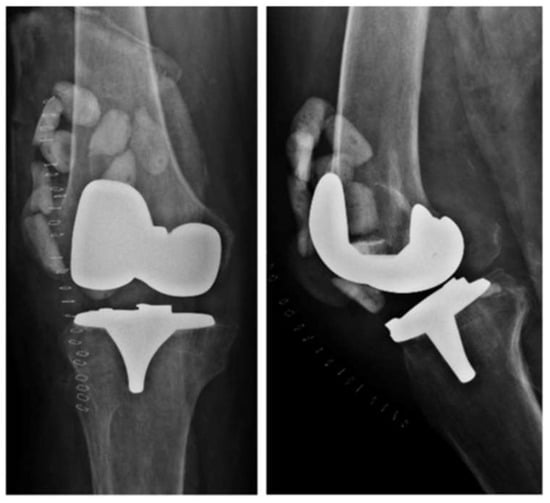

Double DAIR is a technique that, according to the literature, has a higher success rate than single DAIR [28]. After the debridement, irrigation, and replacement of the modular component, high-dose antibiotic-loaded cement beads (vancomycin 3 g/tobramycin 3.6 g) are left in place (Figure 2). Another lavage is performed after 7–14 days, during which the cement beads are removed. The study conducted by A. S. Chung et al. [28] demonstrated that two-stage DAIR is more effective than single-stage DAIR, achieving a success rate of 86.7% in acute PJIs of the hip and knee. Another clinical study by C. S. Estes et al. [29] reported a 90% success rate in patients treated with double DAIR.

Figure 2. X-rays of a right knee with an infected total knee arthroplasty showing cement beads inside the joint capsule.